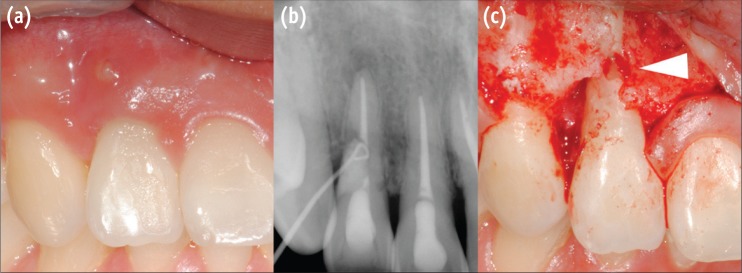

Thirty months after the trauma, the patient came to our department again for regular checkups. The patient was still free of symptoms, but there was a sinus tract formed on labial mucosa of right maxillary lateral incisor. Periapical radiograph was taken with gutta-percha tracing to confirm the origin. Surprisingly on the distal root surface of right lateral incisor, a noticeable cervical defect was revealed. The resorptive lesion was provisionally diagnosed as invasive cervical resorption and surgical repair was attempted (Figure 1).

All procedures were performed under operating microscope (OPMI, PICO, Carl Zeiss, Gottingen, Germany). After local anesthesia (2% lidocaine with 1:100,000 adrenaline), full-thickness periosteal flap was elevated. Soft tissue curettage and initial debridement with low-speed round bur disclosed the characteristic resorptive lesion involving labial and distal surfaces of the root (Figure 2). First, numerous small bleeding points (referred to as 'penetration points' by Schwartz) were observed.6 These indicate that the lesion possesses active resorptive potentials carrying blood supply from the periodontium into deeper parts. The base containing these points was solid on probing. This is a feature of advanced ICR lesions with fibro-osseous tissue replacing resorbed dentin. Failure to differentiate this ectopic calcified material from dentin can lead to failure in treatment, because resorption will continue beneath the apparently sound cavity base.5 Tooth preparation was carried out and intact dentin base was confirmed under high magnification (×16 - 20). The cavity was restored with reinforced glass ionomer (GC Fuji II LC, GC Corporation, Tokyo, Japan) and light cured. Further refinement was achieved with a fine tapered diamond bur. Flap was repositioned and sutured interproximally with 4-0 mersilk (Mersilk, Ethicon, Edinburgh, UK).

One month recall showed satisfactory gingival healing and the patient was free of symptoms. However on the radiograph, suspicious radiolucent spot was observed under the glass ionomer filling, and after another month, sinus tract recurred. Periapical radiograph with gutta-percha tracing definitely shows apically advanced radiolucent lesion under the glass ionomer filling (Figure 3). Treatment options were discussed with the patient and decided to go on a re-surgery. Full-thickness periosteal flap was once more elevated. As predicted, the progressed resorption site was clearly seen under the buccal side of glass ionomer filling. After initial debridement, penetration points in the cavity were visible, again suggesting that there are tissues with active resorption potential left inside. Additional tooth preparation of the remaining resorptive tissue and glass-ionomer filling was done, but considering root stability and associated periradicular pathosis, we decided to extract the tooth (Figure 1).

Figure 2

Microscopic view during surgical repair. Arrowheads indicate penetration points. Note the fibro-osseous tissue resembling dentin on the surface. (a) ×6; (b) ×16 magnification.